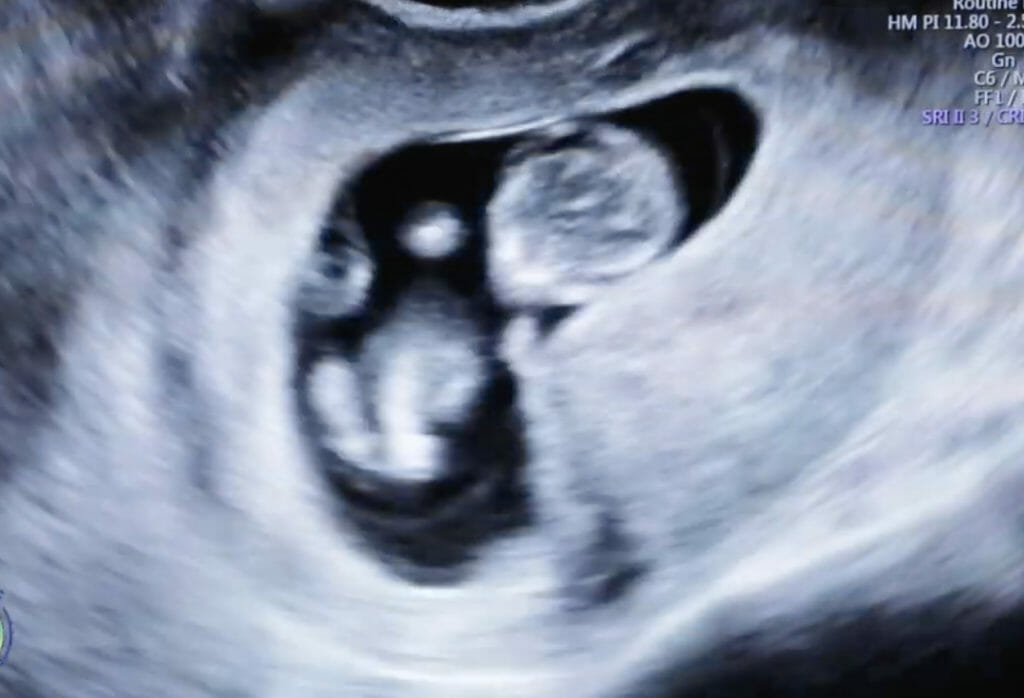

A high resolution ultrasound is the first step in looking at the female reproductive system.